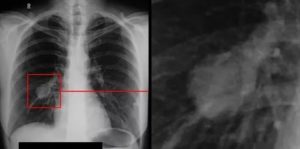

Злокачественная опухоль, представляющая собой скопление клеток с определенным внешним видом. Злокачественные клетки не похожи на обычные и характеризуются бесконтрольным делением и способностью к метастазированию – отщеплению от своего места рождения и распространению в другие ткани.

Как проверить легкие на онкологию? Более тщательное исследование легких можно получить, используя компьютерную томографию. Поперечные срезы грудной клетки и других органов на изображении получаются очень четкие.

Этого нельзя увидеть с помощью трех вышеописанных методов. На томографии видно, как изменилась легочная ткань или трахея, бронхи и лимфатические узлы.

С помощью этого вида обследования можно отследить отклонения, выявить травмы грудной клетки, новообразования на ранних стадиях и воспалительные заболевания. При помощи данного метода можно увидеть патологические изменения легких, бронхов и трахеи на 3D изображении. Детальная картина помогает врачу поставить безошибочный диагноз.